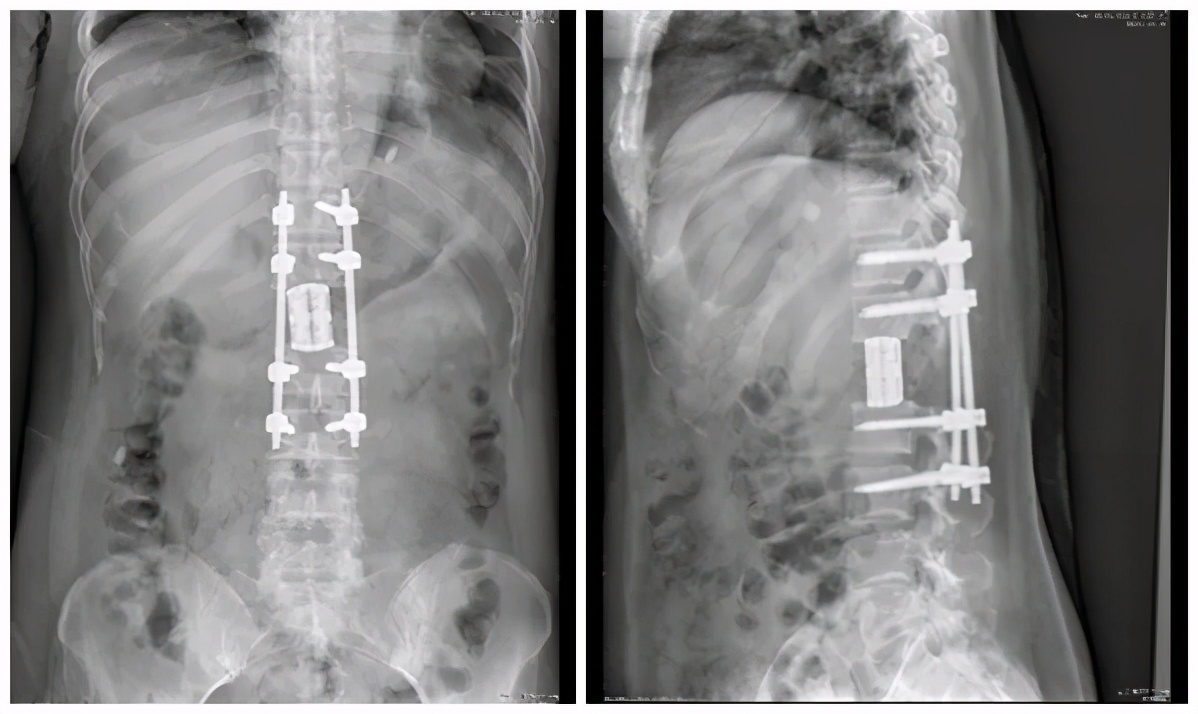

术后DR正位片 术后DR侧位片